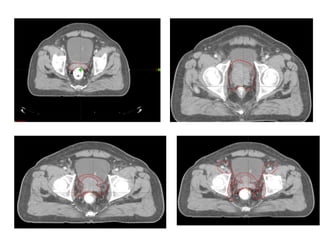

Primary role

• Size determination of the gland

• Assess pelvic LN metastasis

• Treatment planning in RT

Features:

• Loss of periprostatic fat planes

• Bladder base deformity

• Obliteration of the normal angle

b/w the SV and post. aspect of

UB

LN involvement

Abnormality in size

Sensitivity 25%

Reserved for patients with higher

PSA values (>20-25 ng/ml)

CT guided FNAC

Limitation of CT:

• Lacks the soft tissue

resolution needed to detect

intraprostatic anatomic

changes due to primary

tumor , capsular extension or

SVI because the neoplasm

usually has the same

attenuation as the normal

prostate gland

• Can't detect microscopic

disease

• False Positive- Artifact of

Bx and plane b/w SV and

UB base may be obscured

by rectal distension

CT SCAN